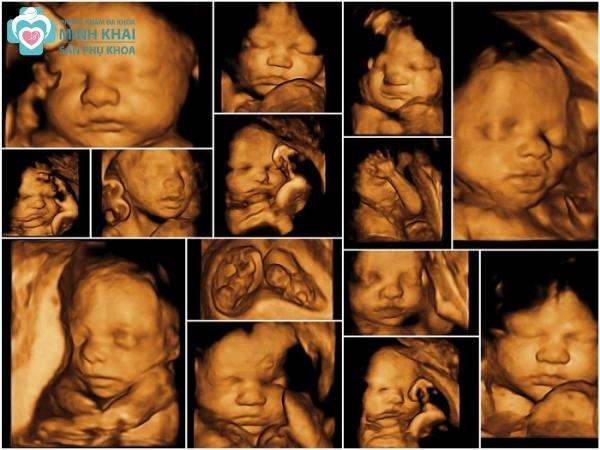

Hình ảnh siêu âm 4D

Hình ảnh siêu âm 4D thể hiện qua ảnh động các chuyển động liên tục của bé con ngay trong thời gian thực khi siêu âm. Thay vì ảnh đen trắng, siêu âm màu 4D cho những hình ảnh có màu sắc với độ phân giải cao và vô cùng chân thực, sắc nét hiển thị rõ trên màn hình. Thêm vào đó, hình ảnh siêu âm 4D còn được máy xử lý tự động cho phép người xem có thể chọn đa dạng các chiều mặt cắt, chế độ xem khác nhau.

Nó có thể chụp lại đầy đủ cấu tạo các bộ phận cơ thể cũng như tái hiện lại các cử chỉ của thai nhi như đạp chân, múa tay, cười,... Chi tiết hơn nữa, kỹ thuật 4D còn giúp quan sát được cấu trúc bộ xương cũng như đa chiều mặt cắt, siêu âm hệ thần kinh, não và tim.

Khi theo dõi hình ảnh siêu âm 4D, ba mẹ còn quan sát được kỹ và chi tiết nhất về đường nét khuôn mặt, giới tính cũng như cấu tạo các bộ phận cơ thể của con. Đây chính là niềm vui được ngắm nhìn từ trong thai kỳ đến lúc con sắp chào đời mà mẹ bầu nào cũng mong muốn.

Điểm vượt trội nhất để siêu âm 4D luôn là lựa chọn hàng đầu cho các thai phụ là khả năng chẩn đoán và phát hiện bất thường, dị tật bẩm sinh. Qua việc phân tích hình ảnh 4D, bác sĩ có thể đánh giá được chính xác khoảng 85% đến 90% những khuyết tật phổ biến của thai nhi. Nhất là các bệnh lý nguy hiểm như tim bẩm sinh, hở môi, mờ da gáy,...